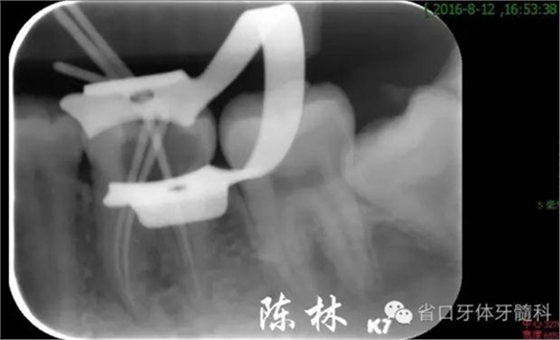

(圖6)試尖片

(圖7)根充片